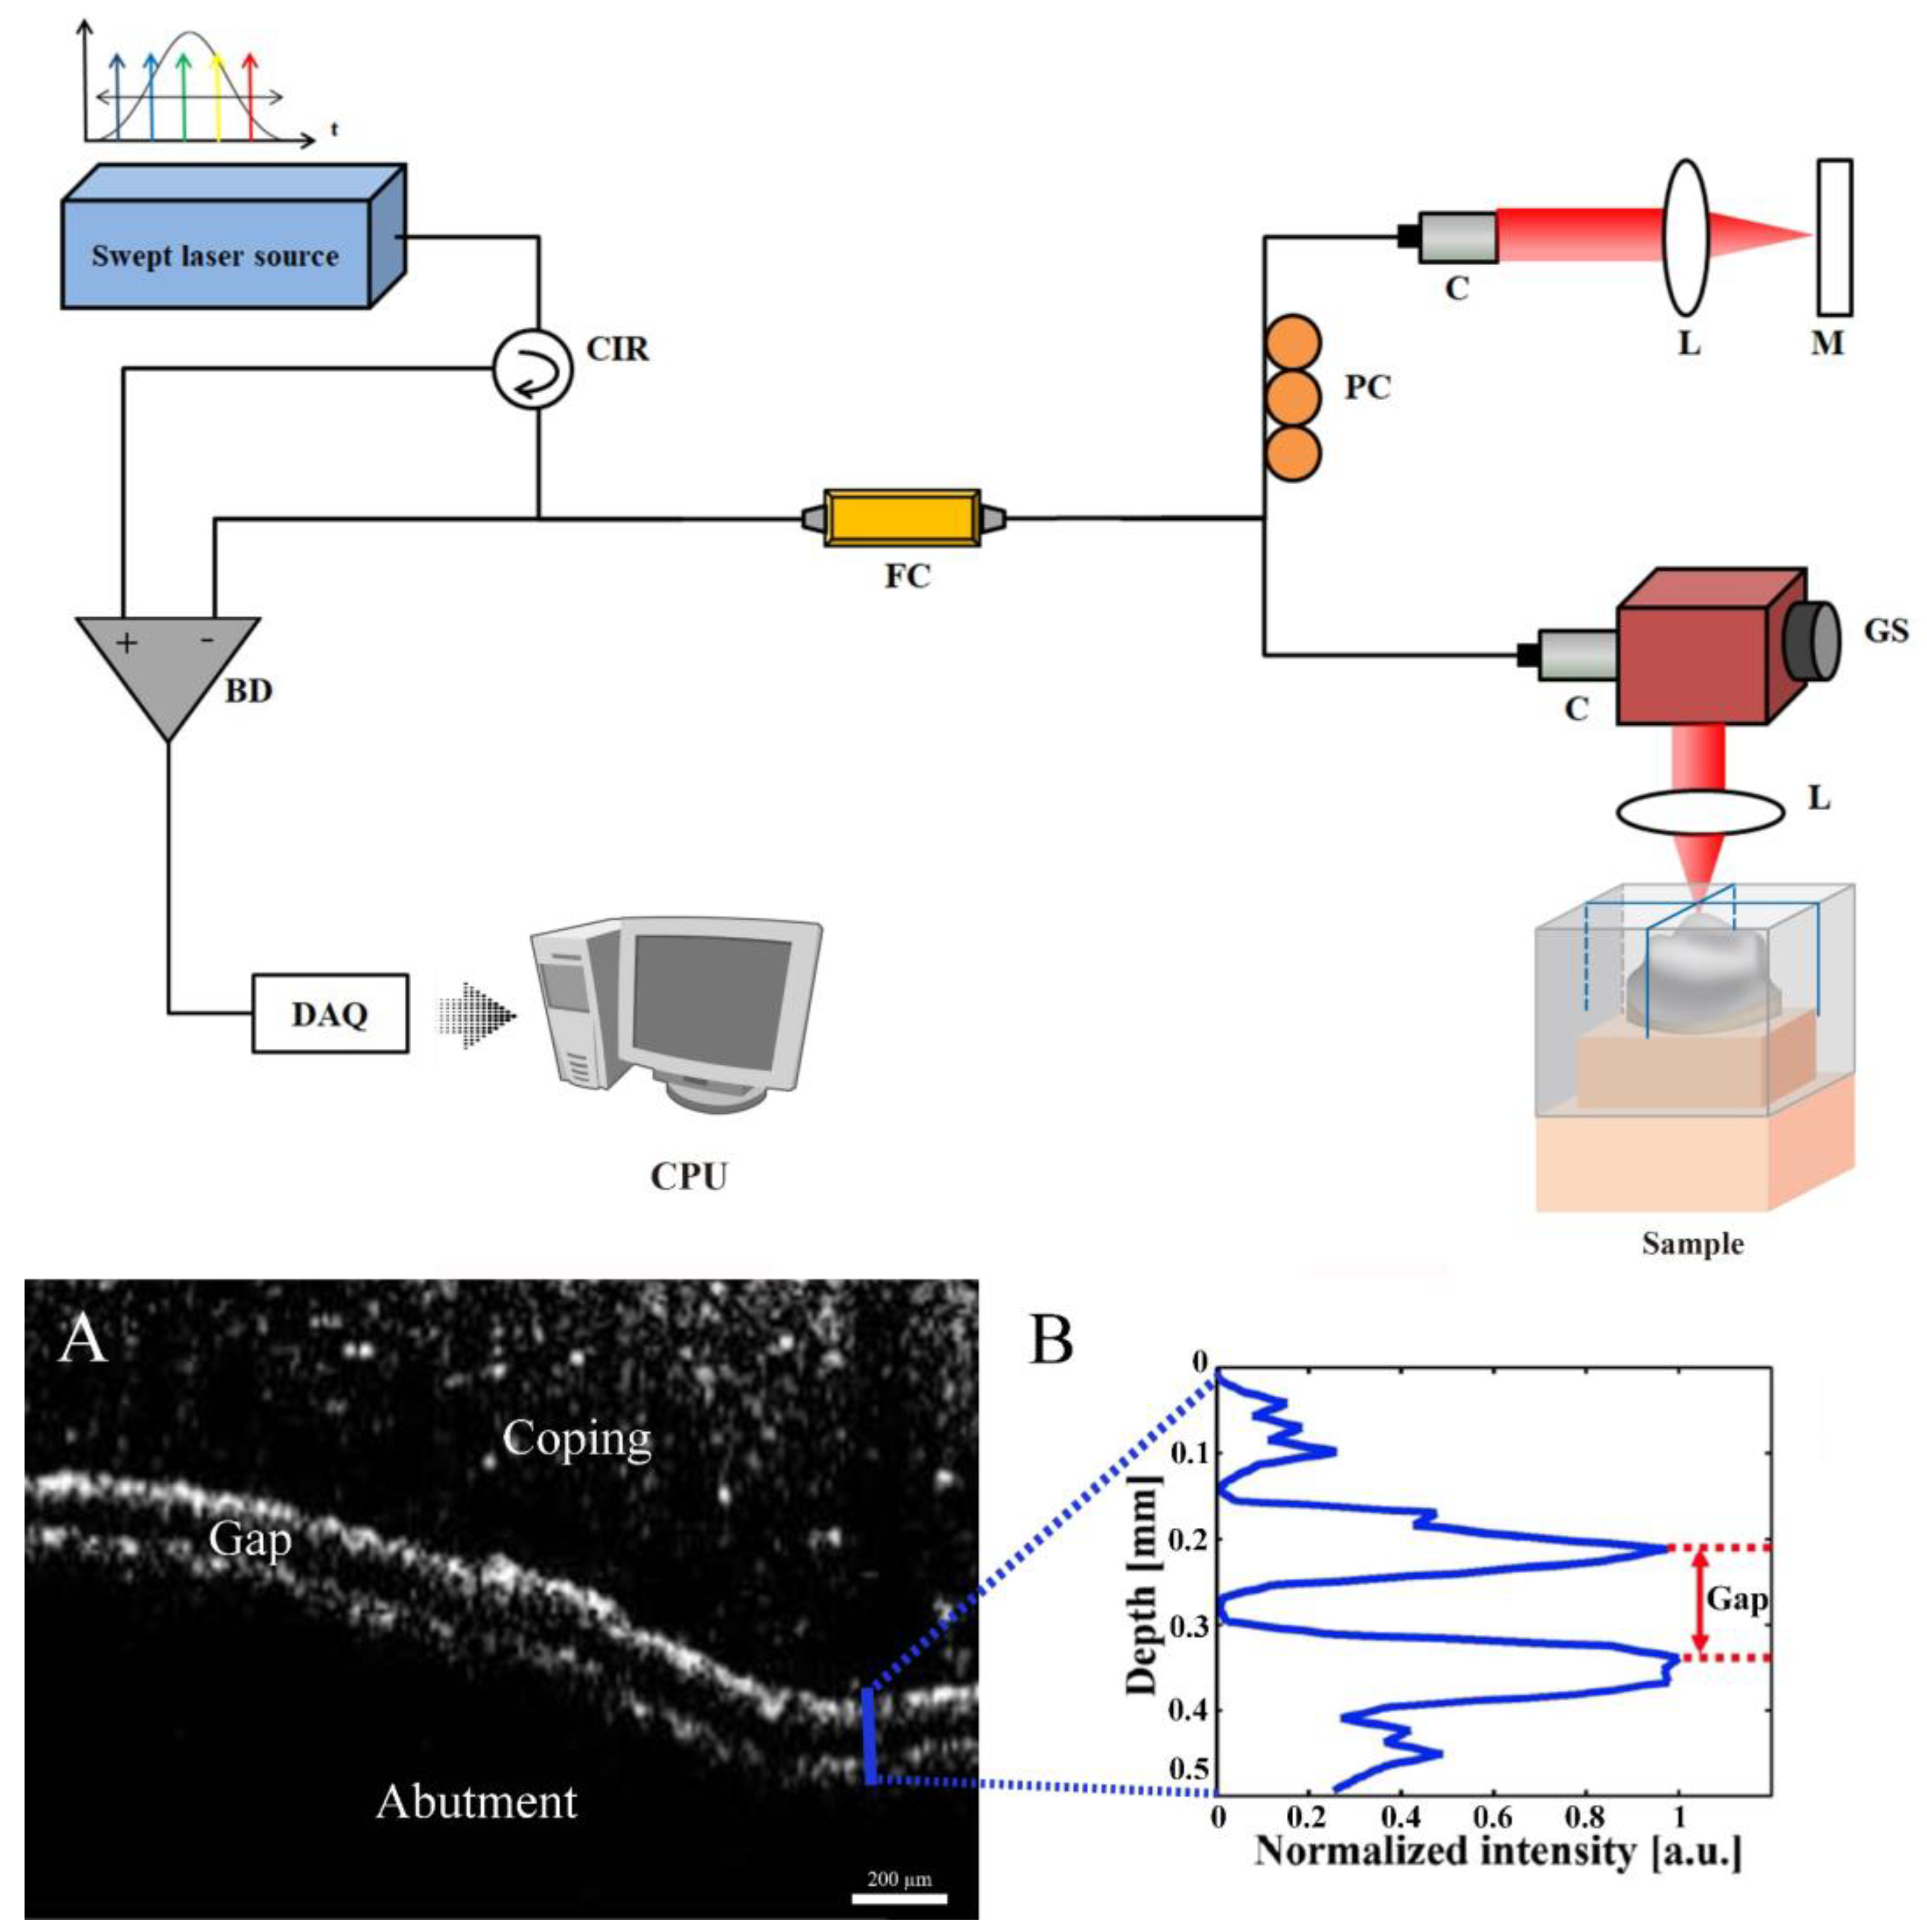

- Optical coherence tomography (OCT): OCT is a method of measurement using higher resolution 2D or 3D images in optical scattering media using coherent light. This is a non-destructive, non-radiological method with the advantage of allowing the acquisition of higher resolution images in real time, which are often utilized for in vivo research [37]. On the other hand, its disadvantage includes difficulty in measuring very thick or optical-opaque materials [16,17,18,19,20,21]. Both 2D and 3D analysis are possible with TSM, MCT, and OCT.

2.2.5. Optical Coherence Tomography (OCT Group)